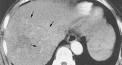

腦部病理改變與病因及病程長短有關。最重要特徵是AlzheimerⅡ型星形膠質細胞廣泛存在於大腦皮質基底核、黑質、紅核小腦齒狀核及橋核等部位程度與神經症狀嚴重程度及病程長短呈正比。慢性病例可見皮質瀰漫性片狀假分層樣壞死皮質與髓質交界處呈腔隙狀態神經細胞及髓鞘變性,部分細胞核內可見包涵體。屍檢腦部有斑片狀皮層壞死或假層狀壞死,皮質髓質連線處、紋狀體和小腦白質內有微小空腔形成。鏡下可見原漿型星形細胞數量和體積均增加。大腦皮層、小腦、齒狀核和豆狀核的神經細胞以及有髓纖維發生變性,星形膠質細胞出現含糖原的核內包含體。

2.腦部CT、MRI掃描有助鑑別診斷。